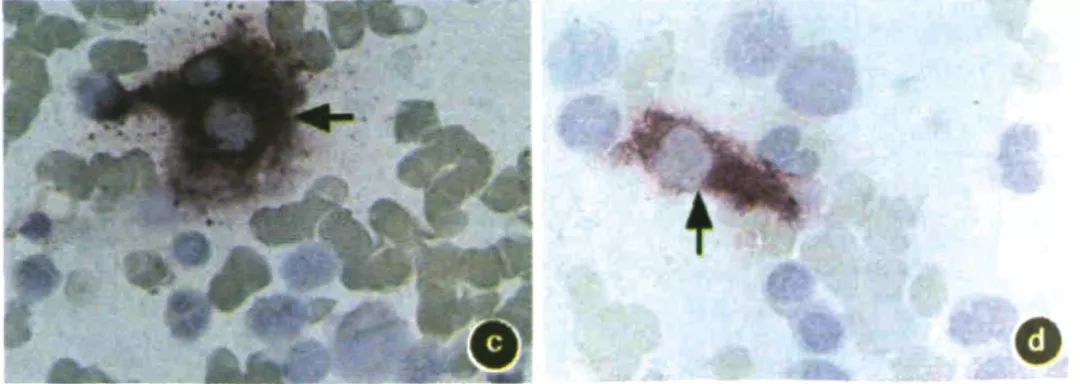

图a~d: 骨髓涂片

a~d图箭头所示为骨髓基质细胞胞质染为紫红色,胞核不着色,而其他细胞均无此染色特征(固紫B盐染色x1000)